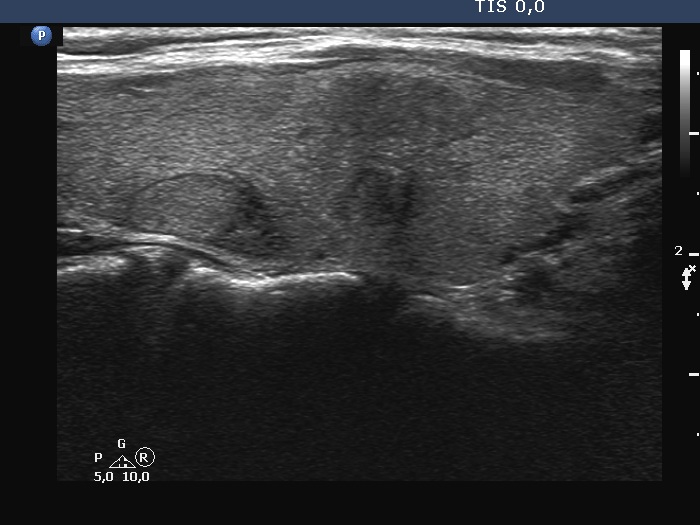

Ultrasonography. The thyroid was echonormal. There were three discrete lesions in the right lobe while several others in the left lobe. There was only one remarkable among them. This was in the ventral part of the right lobe. It was minimally hypoechoic, presented with partly irregular, partly blurred borders. Intranodular vascularity was detected.